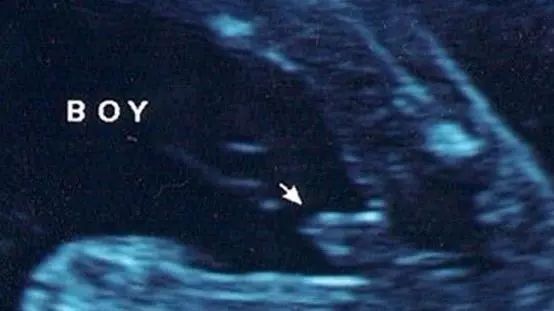

男宝宝B超图

“凸出的东西”是他的标记:你们看到圆圆的是DANDAN,如果看到圆圆的加小肠的就是全部JJ